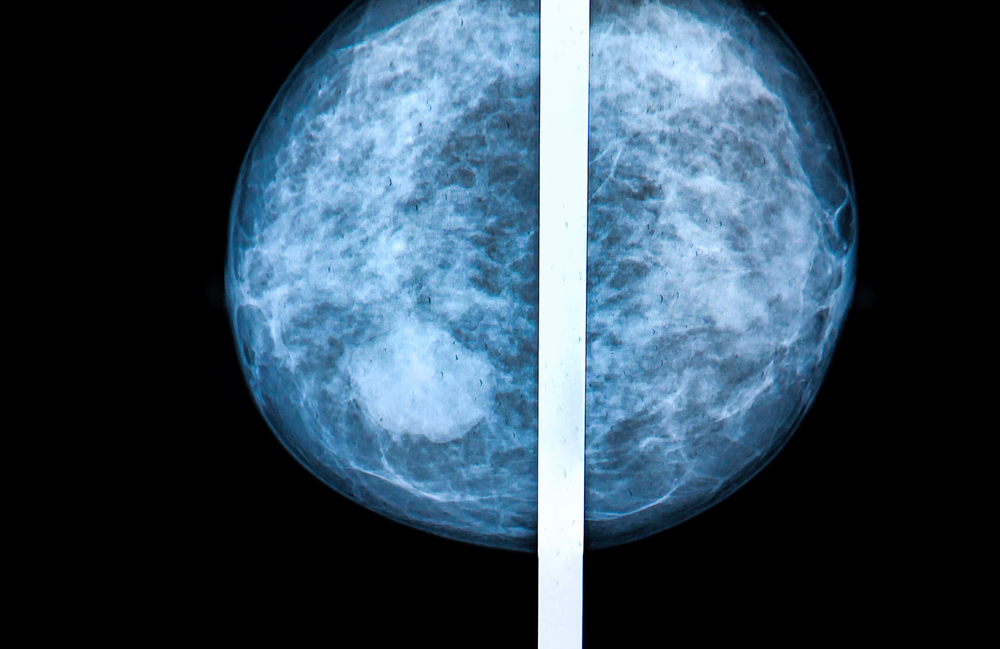

Recently, we wrote about the challenges that women with dense breasts face with mammograms — the primary tool used to screen for breast cancer. Dense breasts make it difficult to detect abnormalities in the tissue. We spoke with ACSH advisor and radiology expert Dr. Robert Bard on the topic [watch our story here], who says identifying dense breasts remains largely subjective. What's more, the presence of dense tissue alone is an independent risk for breast cancer.

We suspected some may take note; but the facts haven't reached as many women as they should. According to a recent study, most women are still unaware that dense breasts are a risk factor for breast cancer. In fact, only 1 in 8 women were aware that density is a risk factor, and just 1 in 5 women were aware that dense tissue reduces the sensitivity of mammograms to find tumors.